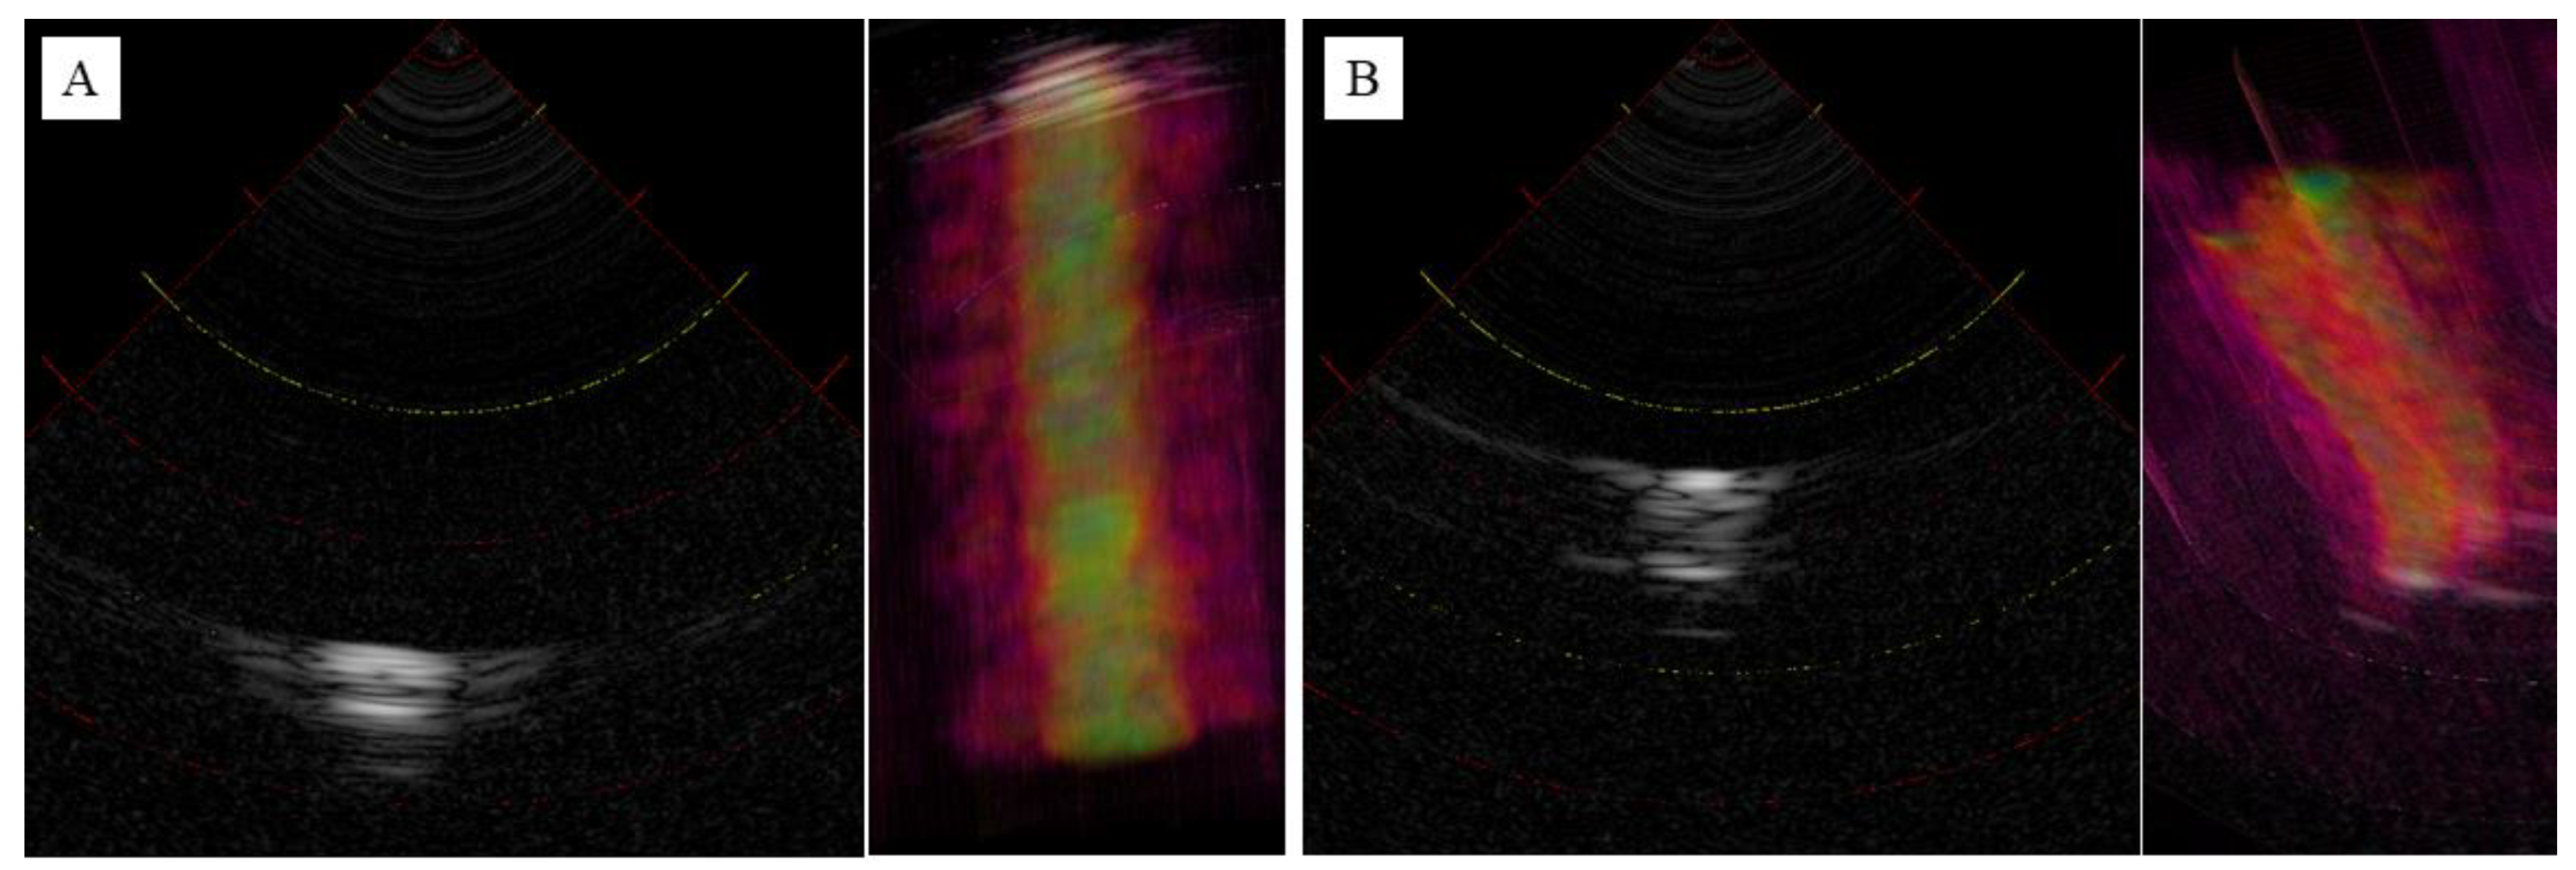

3.2. Observation of the Agar Phantom

4. Discussion